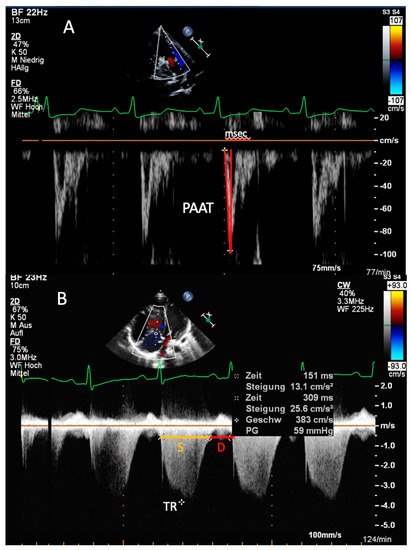

| PAAT | Can be measured in most of PH patients; PAAT < 100 ms in adults—PH is likely; Existing reference values in children | Possible pulmonary valve artifacts; Heart rate dependent (PAAT/RVET ratio is less dependent on age, BSA and heart rate) |

| S/D ratio | S/D duration ratio > 1.4—PH is likely; Geometric independent ratio | Requires presence of defined TR onset/end; Heart rate dependent parameter |